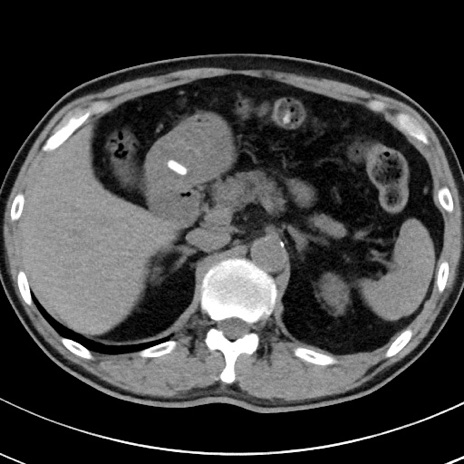

【腹部TIPS】症例29 参考症例 CT(横断像)

症例

70歳代男性